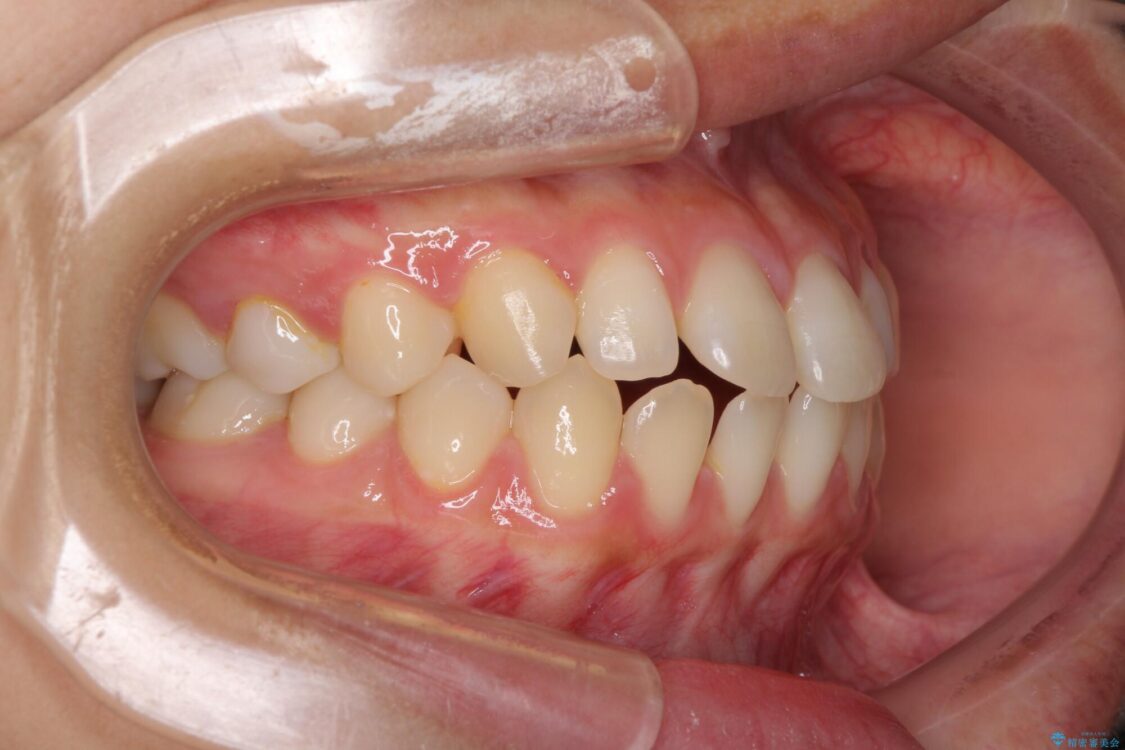

前歯の上下スペースと前歯の隙間を気にして来院された患者様です。

飲み込みや話をするときに舌を突出させる癖が強くあり、それが原因でスペースが空いていました。

舌癖を改善するためのトレーニングを行いながら、インビザラインにより上下の前歯の隙間を閉じていくこととしました。

治療前

• 隙間だらけの歯列 インビザラインで改善 治療前画像